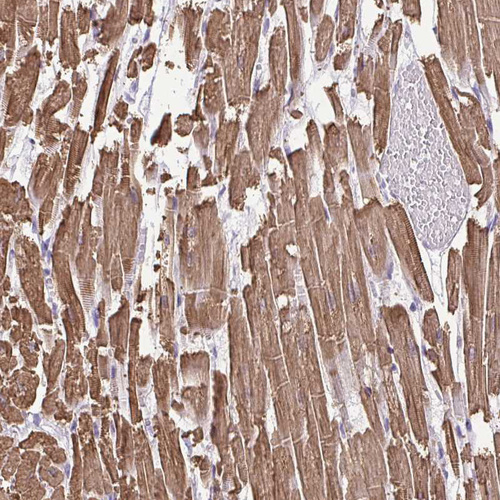

Immunohistochemistry analysis in human heart muscle and pancreas tissues using HPA019763 antibody. Corresponding MYL2 RNA-seq data are presented for the same tissues.